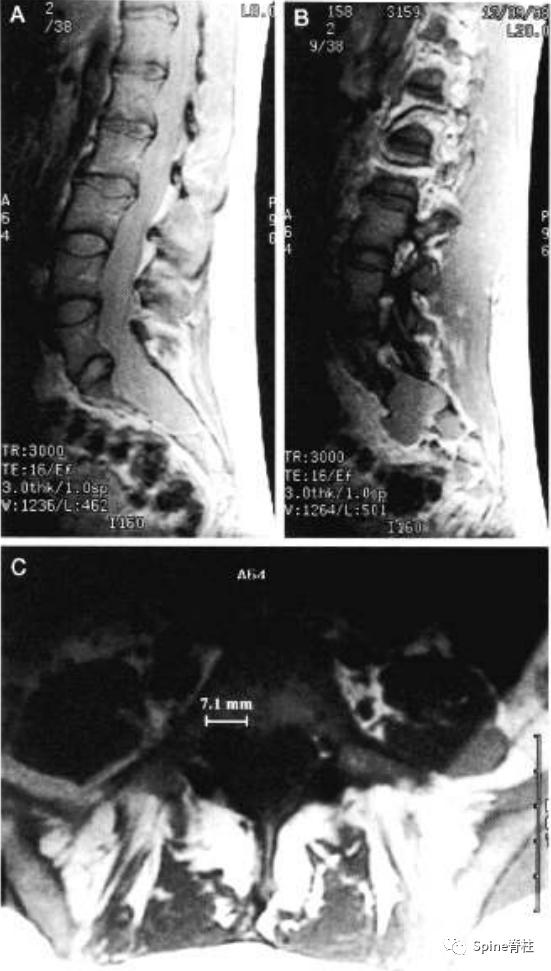

一名18岁男性因腰痛接受MRI检查,下图为矢状位T2(1a)和T1加权像(1b)、S1水平横断面T2(1c)和T1加权像(1d)。

在矢状位T2(2a)和T1加权像(2b)上,多节段椎体后壁呈扇形缺损,缺少硬膜外脂肪(红色箭头),S1处的硬膜囊直径大于L4处。横断面T2(2c)和T1加权像(2d)提示硬膜囊膨胀,S1椎体后壁再次证实硬膜外脂肪缺失(红色箭头)。 其影像学表现符合硬膜扩张的诊断